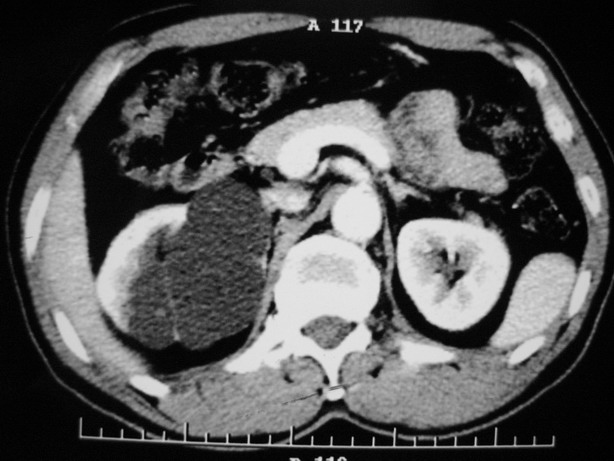

标题: CT10772:男性,48,右肾盂旁多囊性占位! [打印本页]

标题: CT10772:男性,48,右肾盂旁多囊性占位!

男性,48,体检发现,平时无症状。

肾盂旁多囊性占位,有实性成分,增强有轻度强化,收集期病变内无造影剂显影。诊断肾盂旁囊肿,有实性成分无法解释,查书后诊断为:多房性囊性肾瘤!!不知大家同意否?????????对本病知道不多,望大家不吝赐教!!

右肾多发囊性低密度影,囊内有增强的隔及实性组织,考虑囊性肾癌。